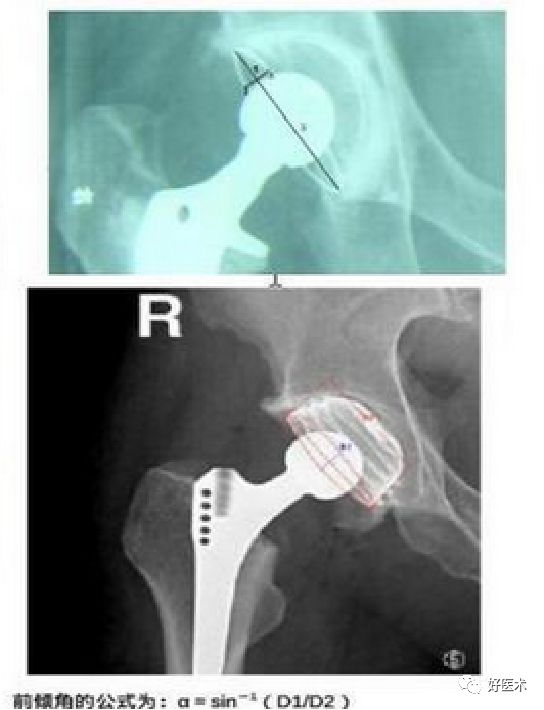

前倾角:15°±10°

正位片上不能区分出前倾或后倾.必须根据侧位片决定。

Pradhan法测量

在X线片上标记髋臼杯口形成椭圆的最大直径D,在最大直径的1/5处标记点M,经过点M做最大直径的垂线并与椭圆相交于两点A、B。测量最大直径D和点M到点A或B的距离P,则髋臼前倾角为arcsin[P/ (0.4D)]